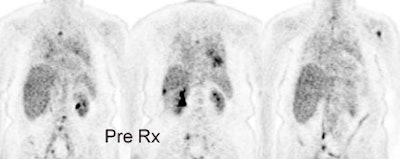

Response to treatment: 58 year old male with a left upper lobe non-small cell lung cancer and contralateral right hilar lymphadenopathy (blue arrow). FDG imaging also identified uptake in the inferolateral aspect of the right hemithorax which most likely represented a pleural metastasis with probable chest wall/rib invasion (black arrow). Because of the advanced stage of disease, the patient received radiation and chemotherapy. Follow-up PET FDG imaging demonstrated decreased tracer uptake and decreased size of the primary lesion in the left upper lobe (red arrow). The metastates in the right hilum, as well as the right pleura or chest wall have virtually resolved. Unfortunately, despite a positive response to treatment the presence of residual FDG activity in this patient would indicate a long term poor prognosis. Case courtesy of the North Texas Clinical PET Institute and CTI. |

Non-small cell lung cancer response to therapy: The patient shown below had widely metastatic left lower lobe lung cancer to mediastinal nodes, bones (left humerus), liver, and multiple pulmonary nodules. Note the dramatic improvement in the patient's post therapy scan (shown below). Click images to view rotating avi files. |